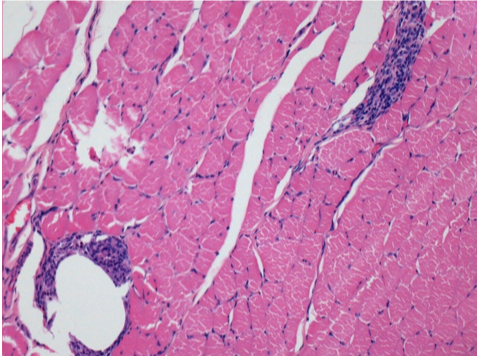

7 months (D210)after Endopeel IM Injection 0.1ml in the right pretibial muscle.

Complete Restitutio ad integrum after 7 months

L :Control 50xD210